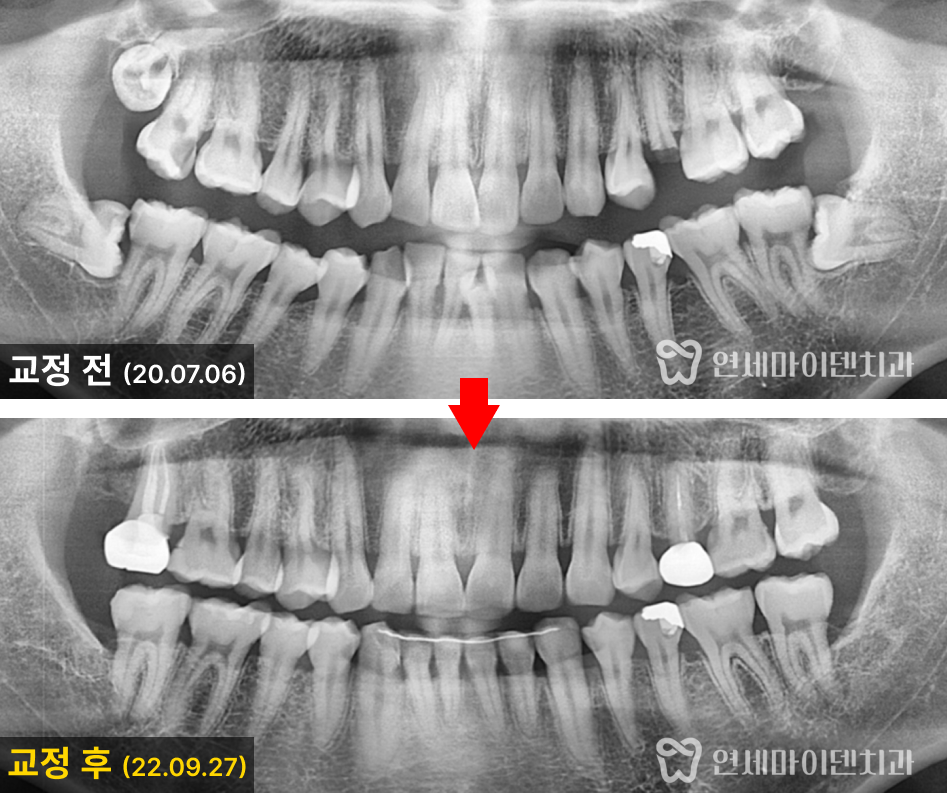

초진 파노라마 방사선 사진을 살펴보니,

왼쪽 위 작은 어금니는 머리 부분이 거의 소실되고 뿌리만 남아 있었습니다.

또, 사랑니가 세 개나 있어 전체적으로 공간이 부족했습니다.

아래 앞니의 겹침이 심했고, 아래쪽 잇몸이 전반적으로 내려가 있어

치주 건강에도 주의가 필요했습니다.

치아 교정은 약 2년 2개월간 진행되었습니다.

사랑니를 발치한 뒤 송곳니부터 뒤 어금니까지

후방 이동을 통해 공간을 만들었습니다.

또, 심하게 겹쳐 있던 하악 전치부를 고르게 배열했습니다.

치료 전 우려했던 잇몸 라인 변화는 최소화되었고,

기능적으로 안정적인 교합을 완성할 수 있었습니다.